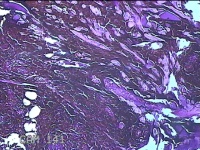

右手臂伸侧肿物

性别

女

年龄

27岁

临床诊断

纤维瘤病

一般病史

下腹部坠胀三天。

标本名称

大体所见

灰褐色肿物0.5x0.3x0.2cm一个,表面糜烂。

图3